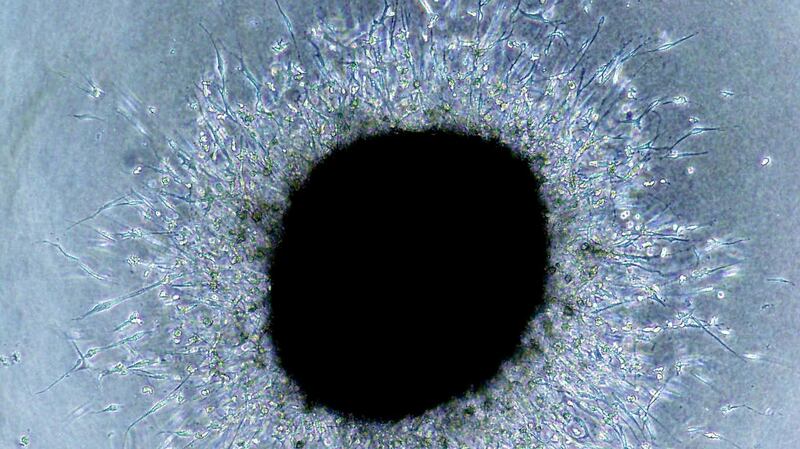

The concept of cancer heterogeneity is not new, but the implications for therapy are becoming more and more apparent. Scientists have been able to take a tumour, separate it into individual cells and label each one with a genetic “barcode”, so that each cell type can be easily identified. They have then implanted the mixture of cells into laboratory animals and followed their evolution.

What they have found is that certain cells are more successful than others and they grow and reproduce faster. All these cells are competing for limited space and resources such as sugar and oxygen and any advantage that a cell has at surviving in this difficult environment results in it growing and reproducing better, taking over and leaving other cells in the dust.

When the tumour runs out of space, some cells might decide to be adventurous and move to greener pastures, spreading to other organs: here they are exposed to completely different circumstances, and only those cells that can adapt to them will prosper.

Sounds familiar? Why yes, this is nothing but Darwinian evolution in action, pure survival of the fittest. Cancer cells are highly variable because of their genetic instability, and then the application of a selective pressure decides which cells come out victorious. These selective pressures can be limited amounts of necessary resources such as sugar or oxygen or, crucially, chemotherapy.